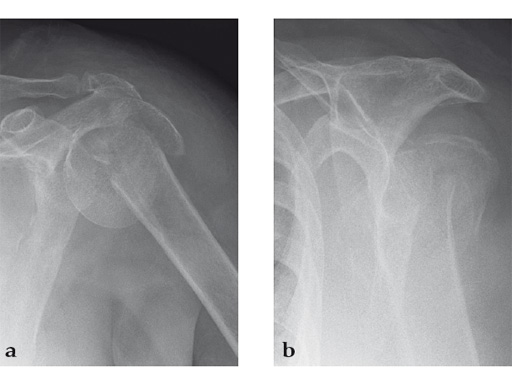

Case 1: A three-part valgus impacted fracture of the proximal humerus in a 47-year-old woman.

Case provided by Stefaan Nijs, Leuven, Belgium